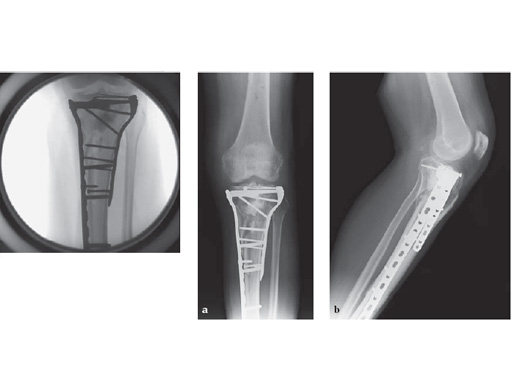

57-year-old malemotor accident

Case provided by Phil Kregor, Nashville, USA